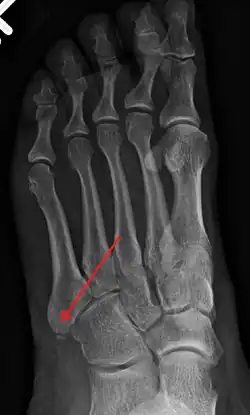

-

X-ray of foot. -